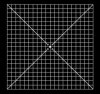

Sarı nokta testi

1)resme tıklayıp gerçek boyutunda açın

2)ekrandan 40-50 cm uzaktan bakın

3)sol gözü kapatıp sağ gözünüzle ortadaki beyaz noktaya bakarken kenarlara dikkat edin.

4)kareli alanlarda bulanıklık,eğiklik,beyaz alanlar,siyah alanlar normal değildir.

5)sağ gözü kapatıp, sol gözünüzle ortadaki beyaz noktaya bakarken kenarlara dikkat edin.